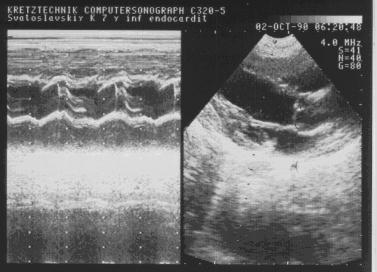

Систолическое трепетание аортального клапана. Бактериальный

эндокардит.

Рис.35.

Систолическое

трепетание

аортального клапана.

Бактериальный